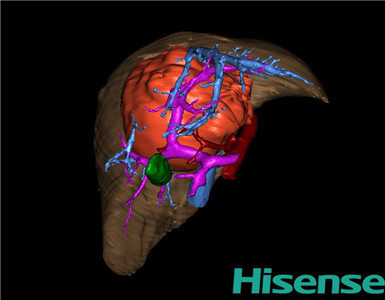

CT结果输入海信CAS系统后行3D重建及手术规划后,于2015-1-8全麻下行“肝脏肿瘤切除术”。

术前三维重建及手术方案设计:

将0.625mm双源薄层CT资料的静脉期和动脉期Dicom格式文件导入海信CAS系统。

通过调节窗宽窗位调整CT序号,对肝实质,胆囊,下腔静脉,肿瘤,肝动脉、门静脉及肝静脉等进行三维重建;系统自动计算肝脏体积。

术前三维重建:

重建图片